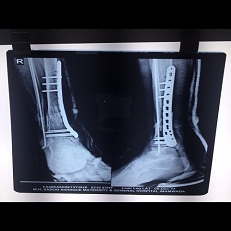

Minimal Invasive Tibia Plating And Fibula Nailing